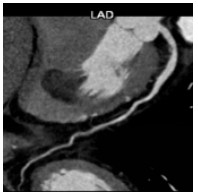

患者进一步进行了冠状动脉的评估。患者能完成活动平板的Bruce极量运动方案,未见心电图心肌缺血性改变。冠脉造影未见收缩期和舒张期冠状动脉有压迫征象。冠状动脉CT造影提示主要冠状动脉分支和肿瘤距离较远(图 6)。

| 图 6 冠状动脉CTA图 |